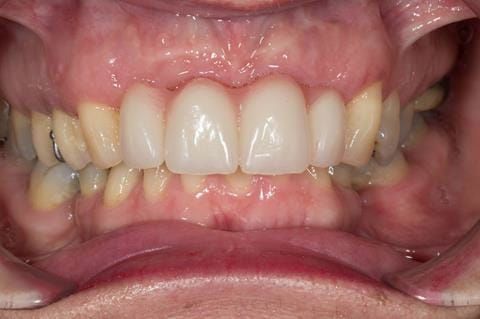

- Extract the upper 2-2 teeth and replace with an interim acrylic based partial denture. Reline the interim denture over 9 - 12 months, replacing with a definitive cobalt chromium based partial denture. The definitive denture would ideally be designed as an occlusal protective splint to reduce the the potential for mechanical wear and breakages of the moderately/heavily restored maxillary dentition. In addition, should further upper teeth require extraction they could be added on to the denture cobalt chromium framework - therefore a new prosthesis would not be required as future teeth are lost. This option would produce an excellent aesthetic outcome. This is the option the patient chose to have.

Following consultation and second discussion appointment the patient chose to have option 3 namely, a maxillary cobalt chromium based partial denture/protective occlusal splint. The clinical situation and treatment process is shown in detail below with photographs. The patient was successfully rehabilitated with this and her quality of life considerably improved. The clinical work was provided by Finlay and the technical work by Rowan.